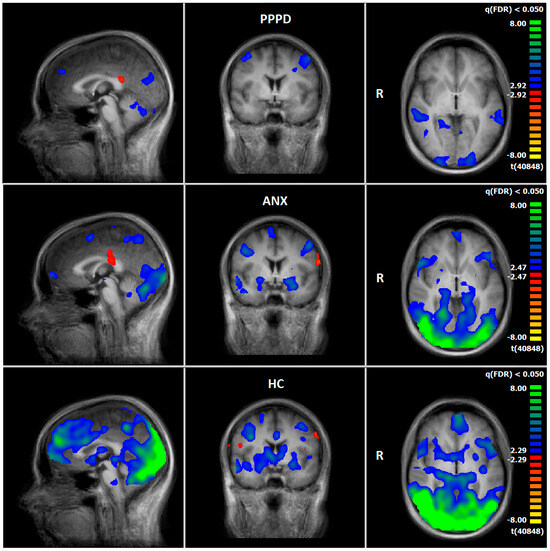

3.4. Comparison of Neuronal Responses Before and After Therapy—PPPD

3.5. Comparison of Neuronal Responses Before and After Therapy—ANX

3.6. HC: Pre–Post Comparison of Neuronal Responses Following a 5–6-Week Interval